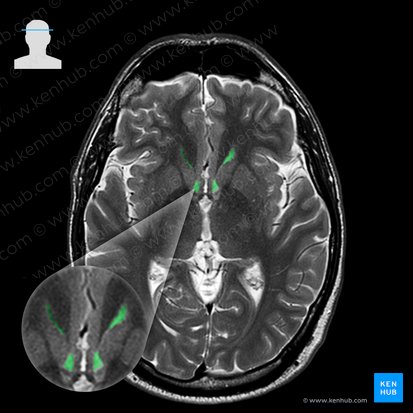

The third ventricle is located between the thalami and below the fornix of the brain. It is normally seen as a slit-like hyperintense structure on the axial brain MRI. It communicates with the lateral ventricles through the foramina of Monro (anteriorly), and with the fourth ventricle via the aqueduct of Sylvius (posteriorly).

After identifying the ventricles, you can quickly assess if there is any pathology related to them. Any squashing or enlarging of the ventricles may indicate ventricular system pathologies, such as hydrocephalus that enlarge them, or nearby tumors, abscesses or hematomas that compress them. Pay attention to observe for any asymmetry, midline shift or displacement. This may indicate mass effect, i.e. the presence of expansive masses that move the brain structures and possibly cause brain herniation. These masses are usually tumors or hematomas, and you would recognize them as the hyperintense collections on T2w sequence, and hypointense on T1w sequence.